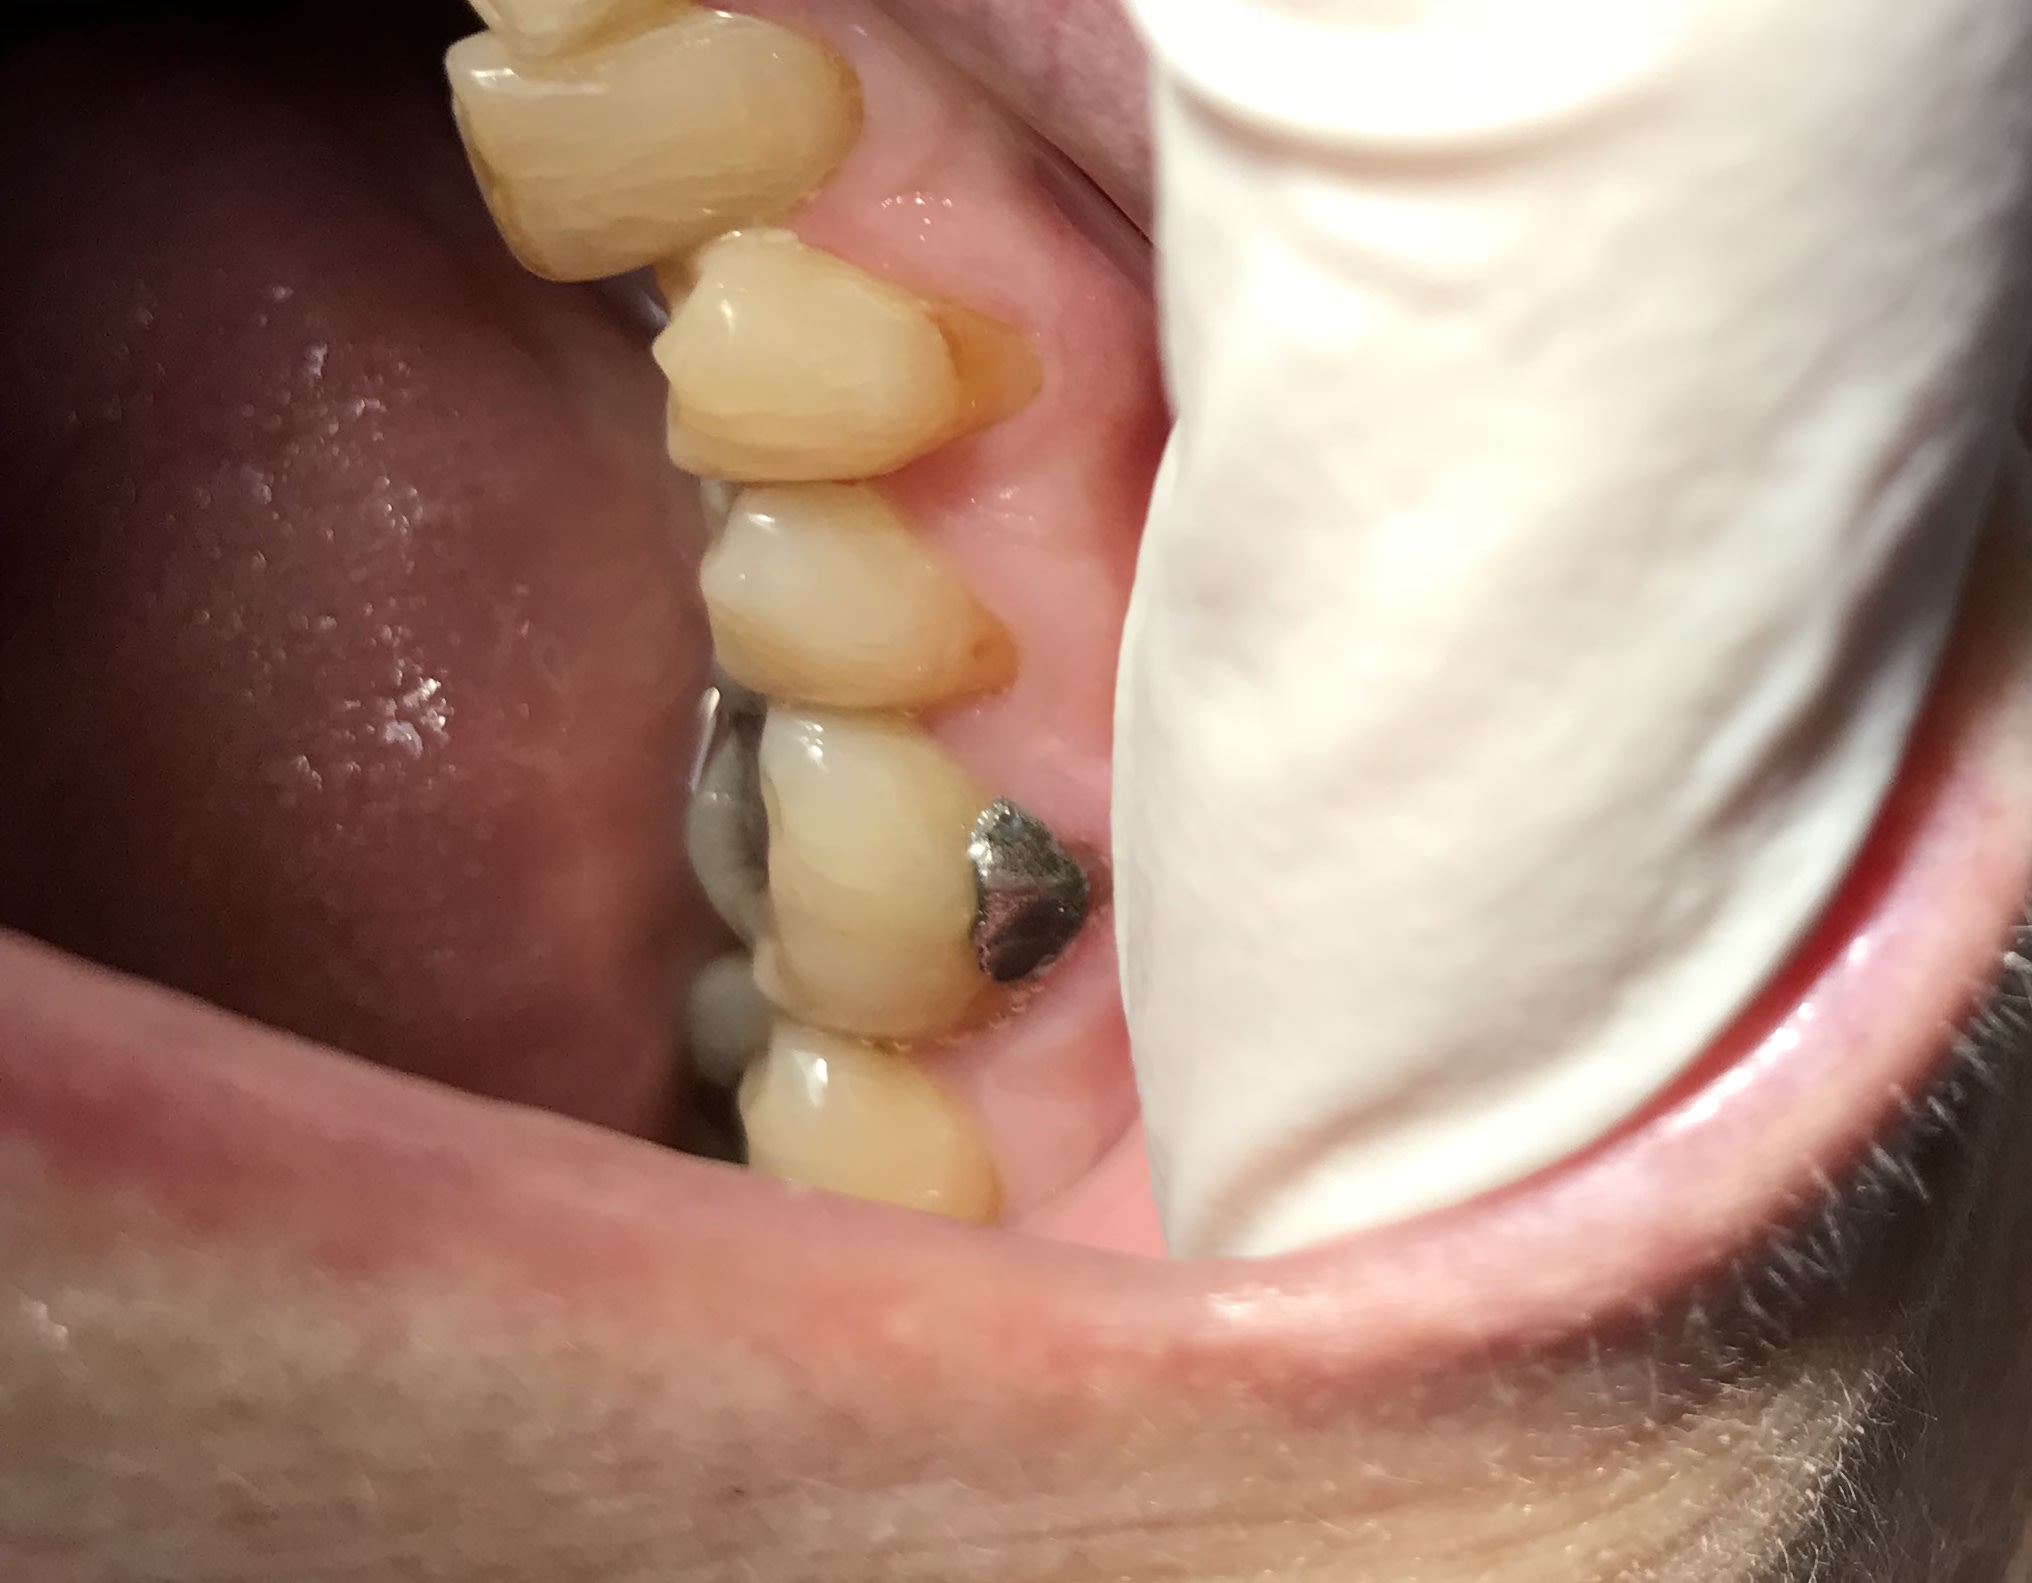

Tiens j’ai un patient qui a été soigné à l’institut Eastman à Paris quand il était jeune (bâtiment en briques rouges) , je connais pas je ne suis pas parisien. Il a ses amalgames qui datent de cette époque : ça fait 54 ans que c’est en bouche. Et Pas de reprises de carie .

Vous m’appellerez quand vous trouverez des composites qui sont toujours en place 54 ans après la pose et sans reprises de carie

L’amalgame ici a plus 30 ans. En V comme ça, on en voit rarement.

Le composite ici a 8 ans

Heureusement que les composites nous ont permis de ne plus avoir ce gris en bouche, un jaune foncé c’est bien plus joli :) . Sur une dent A2 -A1 ça rend bien. Ça a l’air de vraiment bien vieillir le composite. Remarquez quand on le retire on ne tape pas dans la dentine puisque la teinte est bien différente de celle de la dentine ... comme un amalgame finalement.